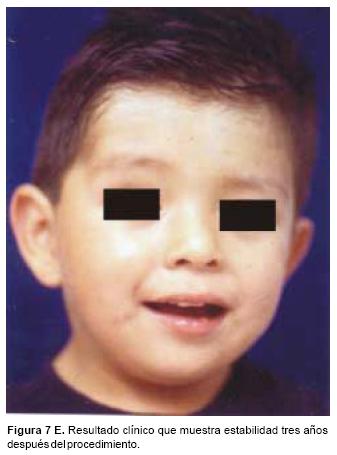

También los controles radiológicos durante el proceso de distracción mostraron que no se produjo la creación de espacios muertos intracraneanos durante los avances. En todos los pacientes con sinostosis bicoronal el avance frontoorbitario produjo excelentes resultados estéticos dando una nueva forma a la región frontal y proyectando mejor el reborde supraorbitario. En los niños con enfermedad de Crouzon y síndrome de Apert, se corrigió en forma muy satisfactoria el exorbitismo al resolver las graves exposiciones corneales (Figuras 5 A, B, C, D, E, F, G, H), en los que se utilizó el avance simultáneo del tercio medio, este cambio óseo corrigió muy satisfactoriamente la retrusión del mismo, ampliando la vía aérea y resolviendo en muchos casos grandes problemas ventilatorios durante el sueño (Figuras 6 A, B, C, D, E, F). Los pacientes con plagiocefalia corrigieron significativamente la deformidad frontoorbitaria y los tejidos blandos suprayacentes se adaptaron a la nueva estructura ósea. La clásica órbita de arlequín de estos niños producida por la sinostosis del frontal con el esfenoides, inmediatamente se ve corregida en su forma y su configuración se hace muy similar con la órbita contralateral (Figura 7)(Fig. 7a, 7b, 7c, 7d, 7e, 7f, 7g) (Cuadro II).